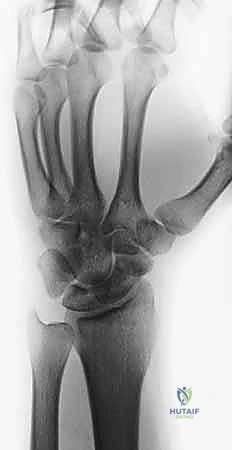

- الأشعة السينية المتقدمة (X-rays): أخذ صور للرسغ من زوايا متعددة ومخصصة (Scaphoid views) لرؤية العظم بوضوح. تُظهر الأشعة السينية في حالات عدم الالتئام وجود فجوة واضحة بين جزئي العظم، وتصلب (Sclerosis) في حواف الكسر، وربما تكون أكياس عظمية (Cysts).

- التصوير المقطعي المحوسب (CT Scan): يُعد الأداة الذهبية لتقييم هندسة العظم. يوضح الـ CT Scan شكل العظم بدقة ثلاثية الأبعاد، ويقيس زاوية التشوه المحدب (Humpback)، ويساعد الجراح في تحديد حجم ونوع الرقعة العظمية المطلوبة بدقة مليمترية قبل الدخول إلى غرفة العمليات.

يتم أولاً إدخال سلك توجيهي دقيق (K-wire) للتأكد من المحاذاة المثالية تحت جهاز الأشعة السينية المباشر (C-arm) في غرفة العمليات. ثم يتم تمرير المسمار فوق السلك. يتميز هذا المسمار بأنه يضغط شظايا العظم والرقعة معاً بقوة شديدة، وبما أنه "بدون رأس"، فإنه يُدفن بالكامل داخل العظم تحت الغضروف المفصلي، مما يمنع أي احتكاك أو ضرر لباقي عظام الرسغ. في بعض الحالات المعقدة، قد يتم استخدام أسلاك كيرشنر (K-wires) إضافية لزيادة الاستقرار.